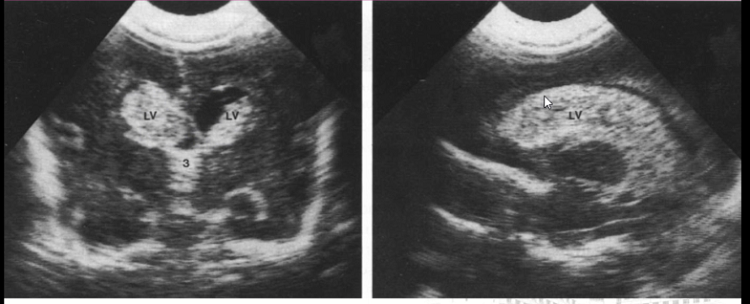

640 (4)

脑室周围白质软化症

640 (5)

脑膜炎脑室炎超声